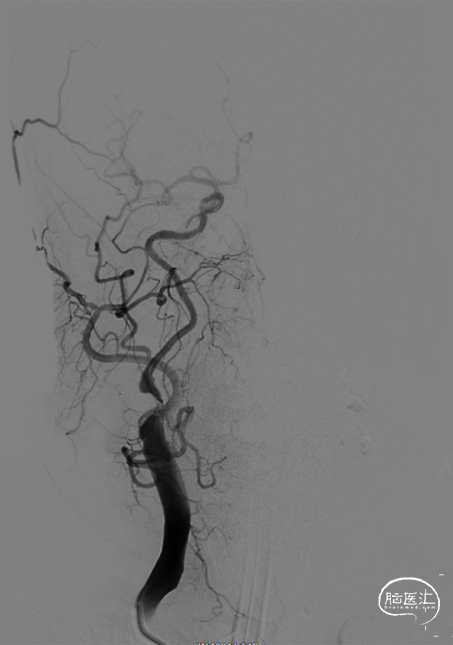

全身麻醉,右侧股动脉入路,常规行右侧颈内动脉造影,造影见右侧颈内动脉起始段重度狭窄,前向血流mTICI 2a级,远端血管床略塌陷。

将9*40mm 颈动脉支架送达目标区域,冒烟确认释放位置满意,释放支架。常规造影,血管成型满意,残余狭窄不足40%,前向血流mTICI 3级,远端血管未见缺如,收伞,伞内未见血栓。醒麻后病人清醒,安返病房。